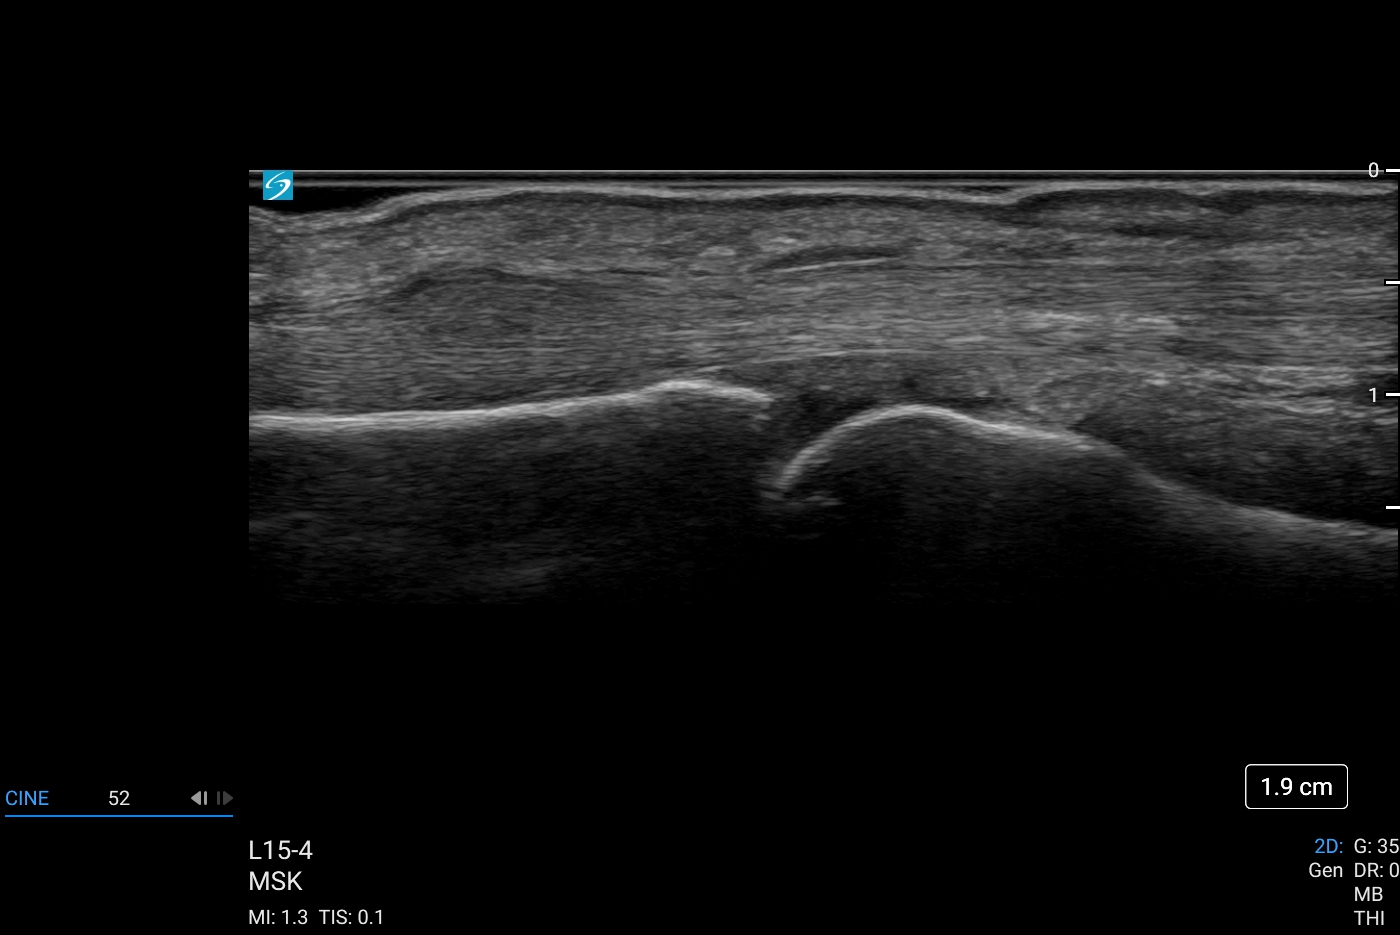

Sonosite LX, bakım noktası ultrasonunu çeşitli ortamlarda daha kapsayıcı ve erişilebilir hale getirerek klinisyenlerin deneyimini yükseltiyor. Sonosite LX, optimum hasta bakımı için en gelişmiş görüntü netliğimizi ve ses kontrolümüzü bünyesinde barındırıyor. Eğitim potansiyeliyle dolu olan bu ürün, her seviyedeki kullanıcıya her zamankinden daha fazlasını keşfetme gücü veriyor.

- Klinik ekip üyeleriyle kolay görüntüleme ve hastalarla konsültasyon için büyük, uyarlanabilir klinik ekranda gelişmiş görüntü netliği